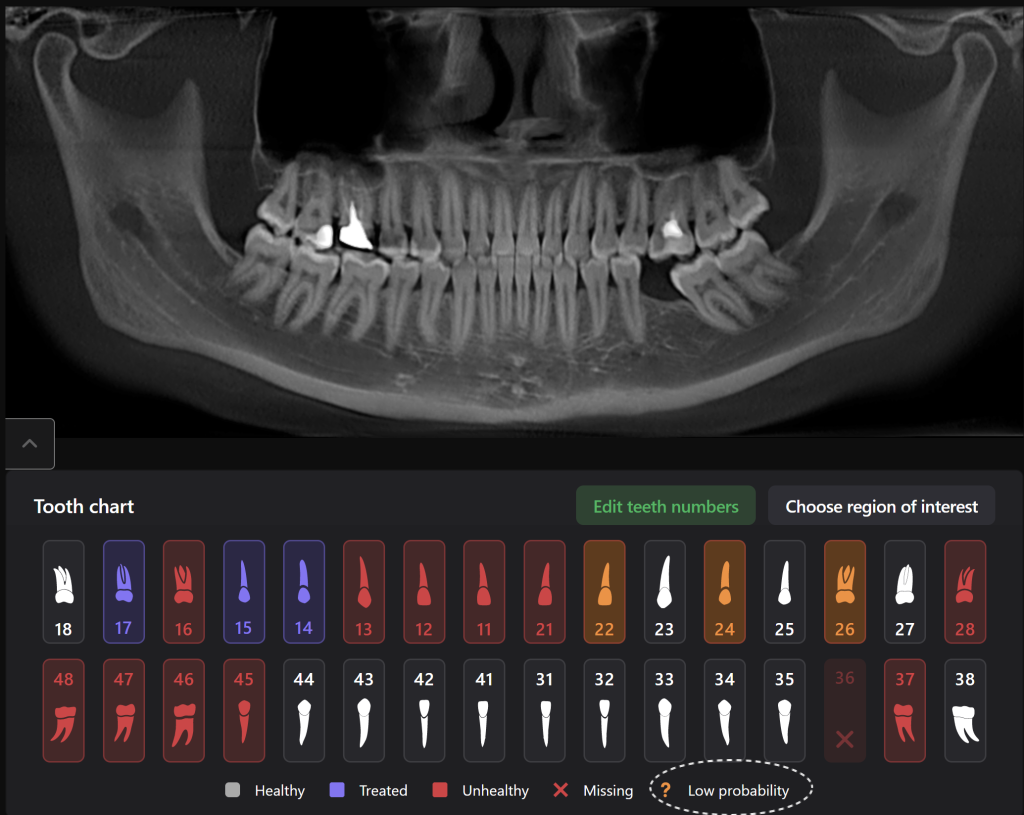

Diagnocat radiological report features an “Conditions with low probability” function. In this mode, teeth marked as “Low probability” are highlighted in yellow. Conditions such as caries and periapical lesions with a probability ranging from 30% to 50%

For example, in the area of tooth 22 (Universal 10), there is a label indicating “signs of caries.” However, they are poorly visualized at the CBCT

Additionally, thanks to the “Conditions with low probability,” signs of caries have been detected on the distal surface of tooth 24 (Universal 12)

If the probability percentage is over 50%, the teeth are highlighted in red, and the report contains information about the localization and depth of the lesions

The presence of caries on the distal and mesial surfaces of tooth 47 (Universal 31) has been clinically confirmed